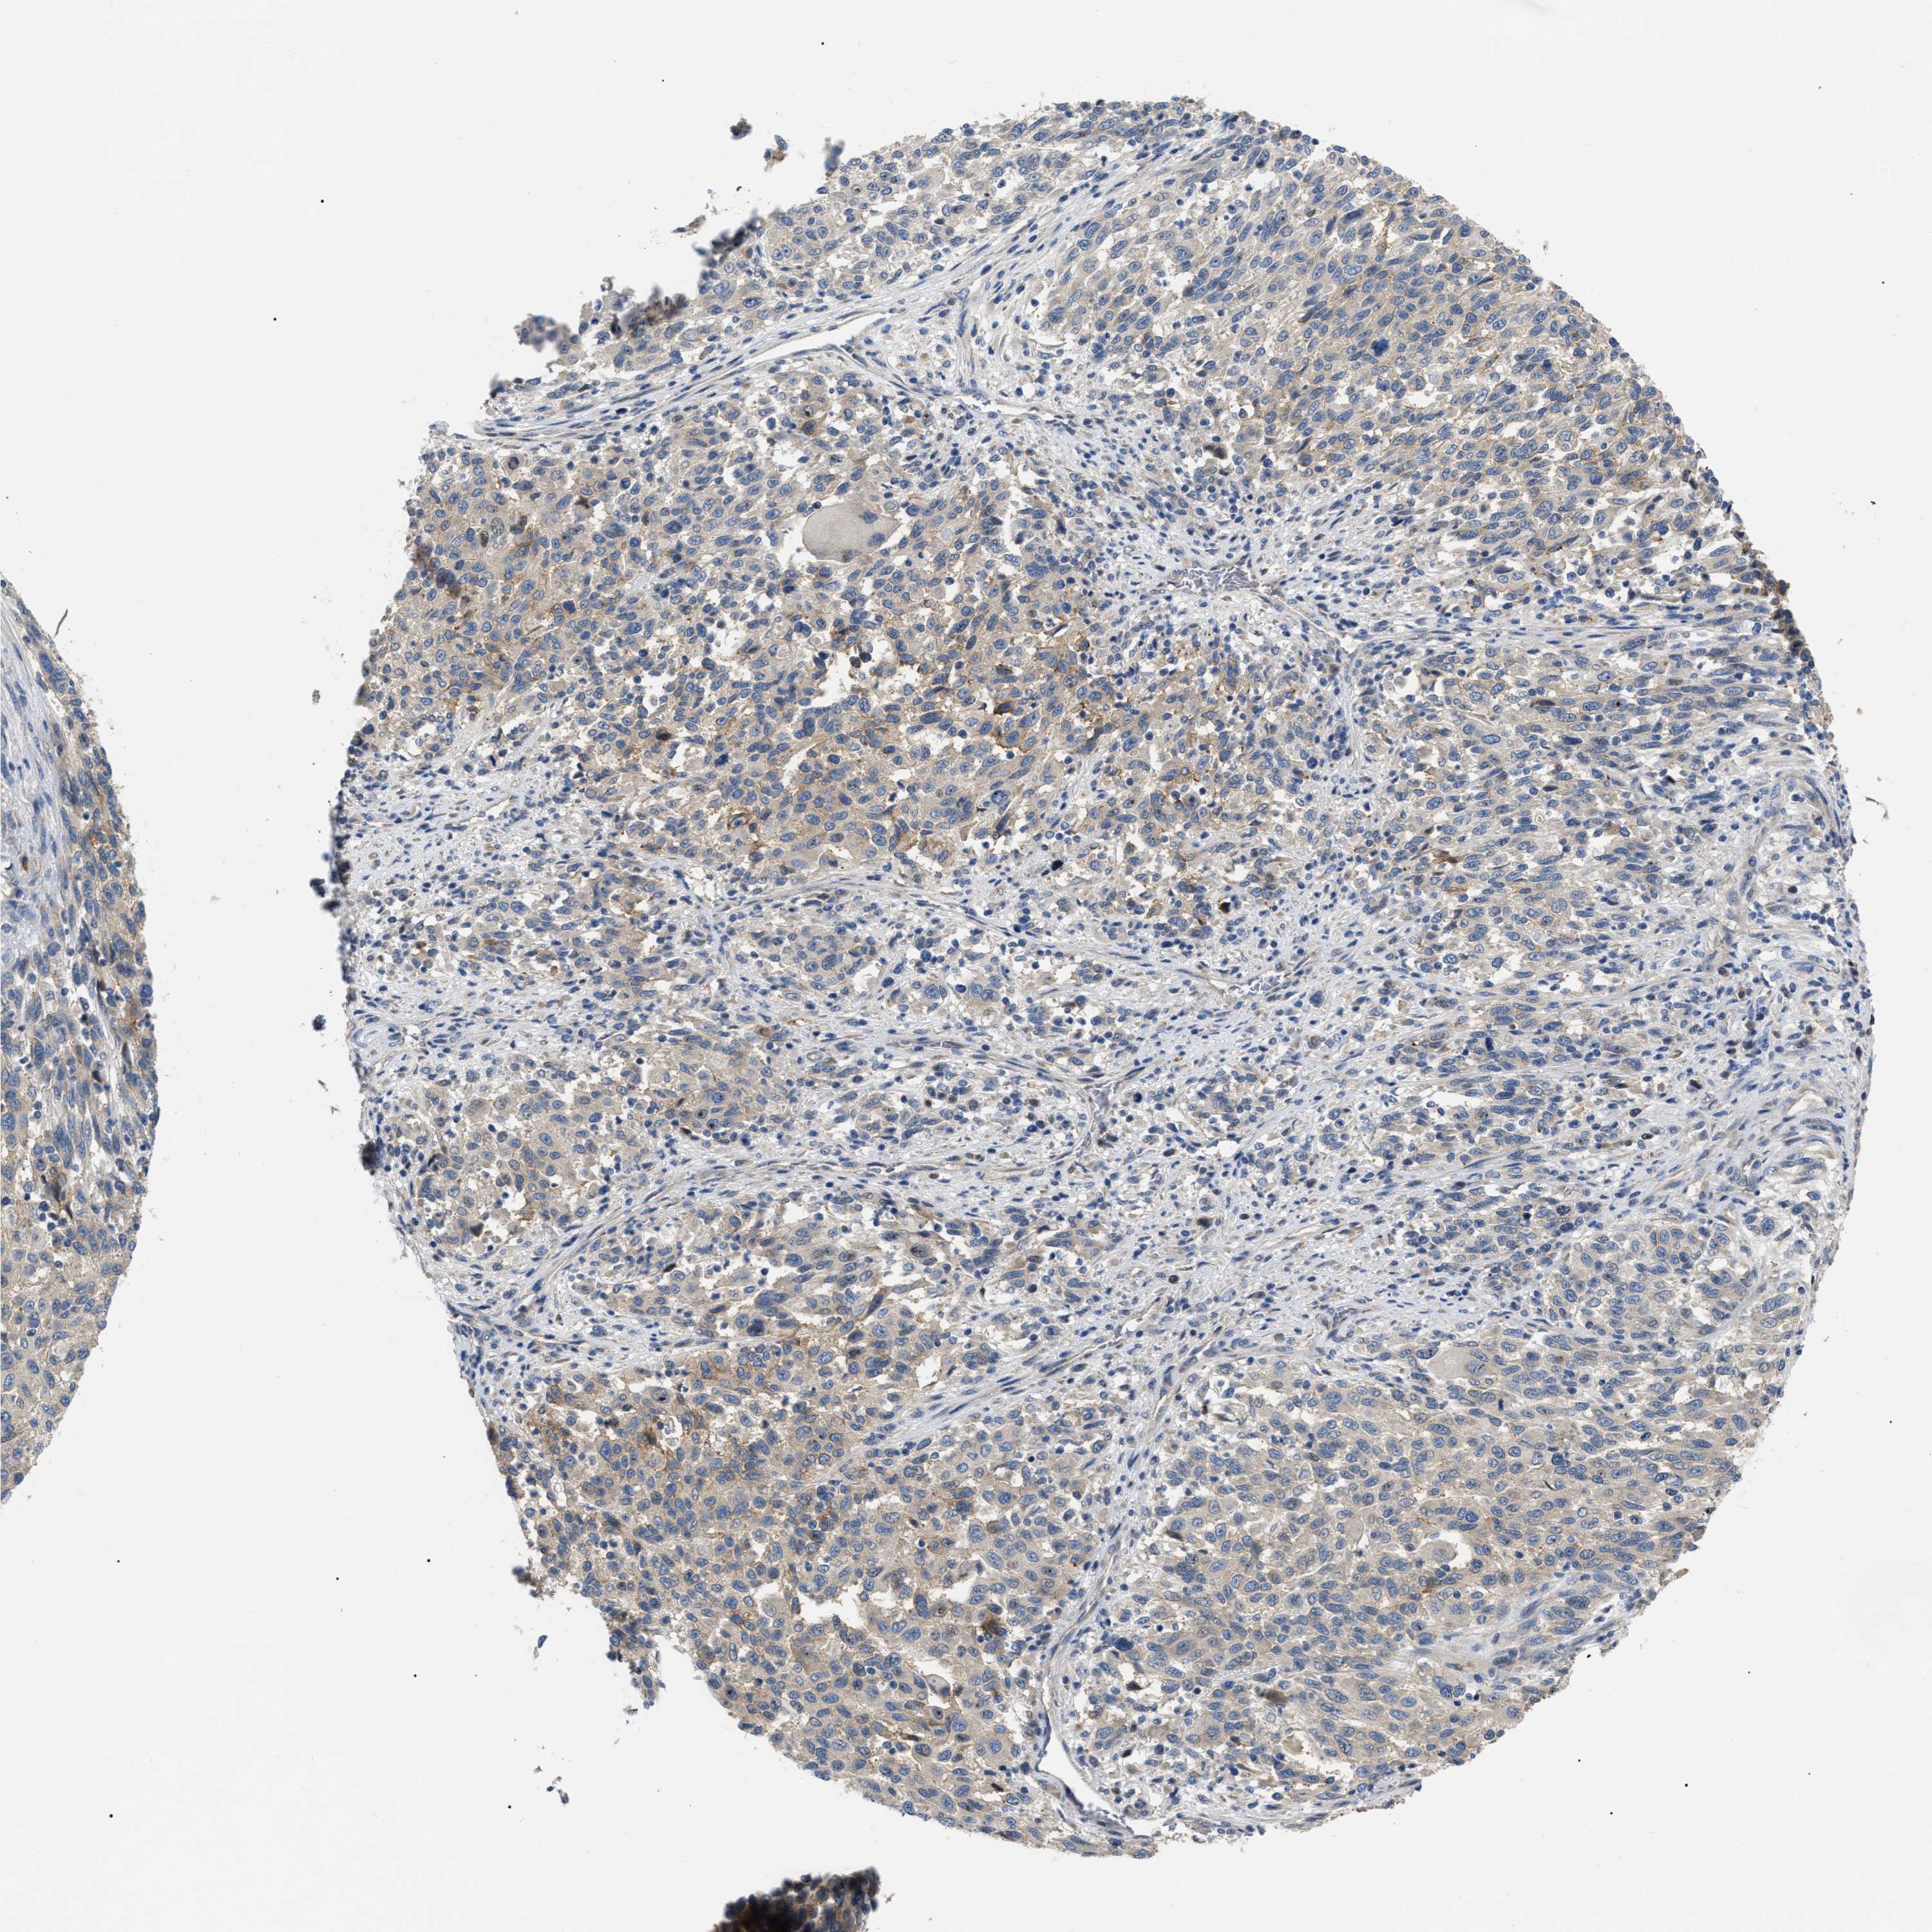

MELANOMA - Protein expressioni

A mouse-over function shows sample information and annotation data. Click on an image to view it in a full screen mode. Samples can be filtered based on level of antibody staining by selecting one or several of the following categories: high, medium, low and not detected. The assay and annotation is described here.

Note that samples used for immunohistochemistry by the Human Protein Atlas do not correspond to samples in the TCGA dataset.

Antibody stainingi

Antibody staining in the annotated cell types in the current human tissue is reported as not detected, low, medium, or high, based on conventional immunohistochemistry profiling in selected tissues. This score is based on the combination of the staining intensity and fraction of stained cells.

Each image is clickable and will lead to virtual microscopy that enables deeper exploration of all samples and also displays staining intensity scores, fraction scores and subcellular localization as well as patient and tissue information for each sample.

Antibody HPA018670

Antibody HPA019570

Malignant melanoma, NOS

Malignant melanoma, Metastatic site